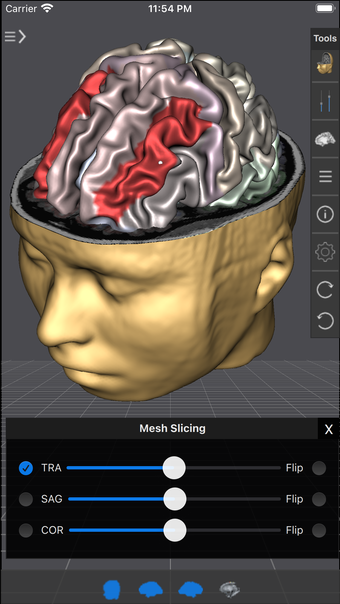

Brain Tutor 3D é um aplicativo educacional gratuito disponível para iPhone, que permite explorar a anatomia e a funcionalidade do cérebro humano através de modelos 3D interativos. Os usuários podem visualizar modelos de alta resolução e realizar cortes em tempo real, utilizando dados de ressonância magnética (MRI) para obter detalhes milimétricos das estruturas cerebrais. O aplicativo é ideal para estudantes, profissionais de saúde e entusiastas da neurociência, oferecendo uma rica fonte de informações sobre lobos, giros, sulcos e áreas funcionais do cérebro.

Com recursos como rotação de modelos em 3D, visualização de tratos de fibra branca e a capacidade de alternar entre diferentes modos de navegação e corte, Brain Tutor 3D proporciona uma experiência de aprendizado imersiva. Os usuários podem interagir com os modelos, aprender sobre a localização das estruturas cerebrais e acessar informações detalhadas sobre cada área. A interface é intuitiva, permitindo uma exploração fácil e educativa do cérebro humano.